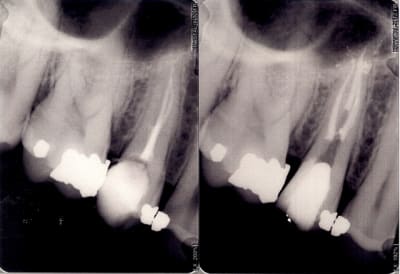

besoin en urgence de photos (enfin radio) de traitement endodontique ou tout autres choses qui demontre bien que mere nature est juste joueuse...dans l'heure qui suit..merci d'avance pour vos perles

classique

classique avec la radio